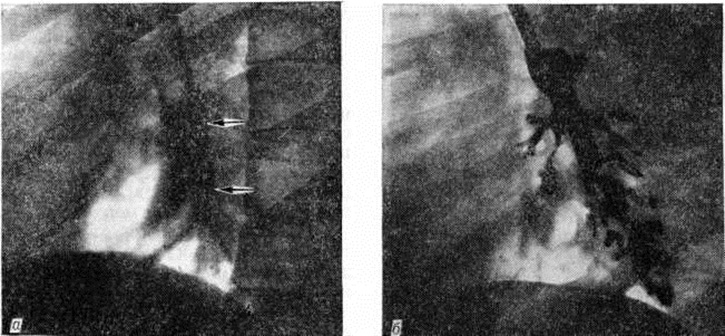

Рис. 8.

Фрагменты рентгенограммы (а) и бронхограммы (б) левого лёгкого при ограниченном пневмосклерозе (боковая проекция): а — уплотнение стромы (указано стрелками) и уменьшение размеров нижней доли лёгкого, б — мешотчатые и цилиндрические бронхоэктазы.

Обнаружение на обзорных рентгенограммах и томограммах описанных изменений служит основанием для выполнения бронхологического исследования. Бронхография (смотри полный свод знаний) позволяет обнаружить сближение, деформацию и неровность контуров бронхов, а также различного типа бронхоэктазы (рисунок 8). Нарушение сократительной способности бронхов (бронхоспазм, бронходилатация, дискинезия) сочетается с изменением скорости и равномерности заполнения их контрастным веществом; периферические бронхи при этом не контрастируются.